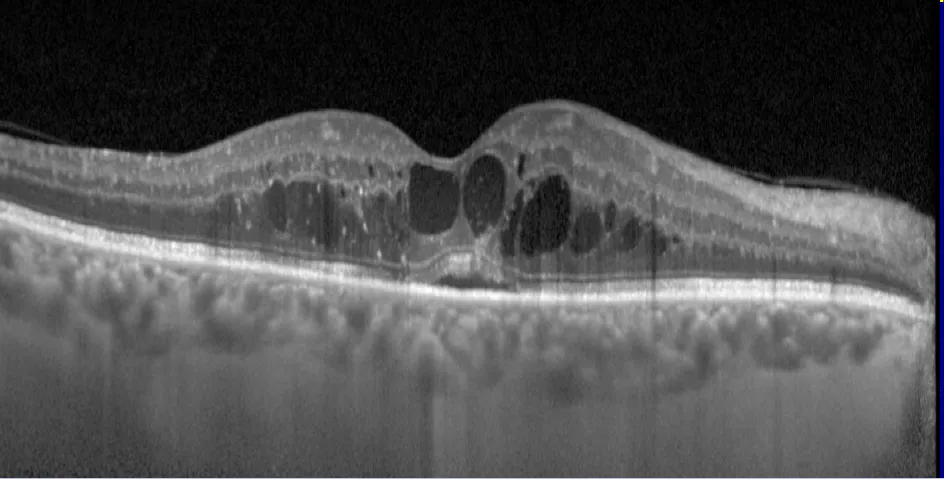

Image d'OCT-ANGIOGRAPHIE d'une CRSC compliquée de Néovaisseaux Choroïdien

Chronic central serous chorioretinopathy imaged by optical coherence tomographic angiography.

Quaranta-El Maftouhi M, El Maftouhi A, Eandi CM.

Am J Ophthalmol. 2015 Sep;160(3):581-587.e1. doi: 10.1016/j.ajo.2015.06.016. Epub 2015 Jun 29